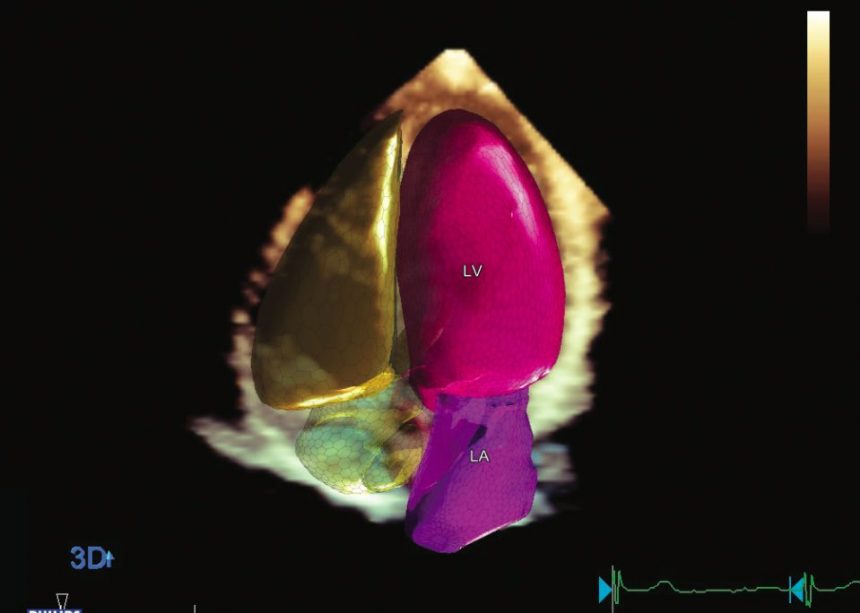

El reconocido cardiólogo argentino Martin Lombardero llega a la ciudad con una muy interesante propuesta para la excelencia del diagnóstico cardiovascular: el mejor equipo de ultrasonido (Eco) cardiovascular, un ecocardiógrafo PHILIPS EPIQ CVx, que incluye un software de Inteligencia Artificial y 3D Cardíaco (Autostrain y Heart Model), Eco-Transesofágico 3D con Transiluminación y 3D Real Time, Cardiac TrueVue, 3D Vascular (inédito en la región), Eco Estrés y múltiples funciones más.